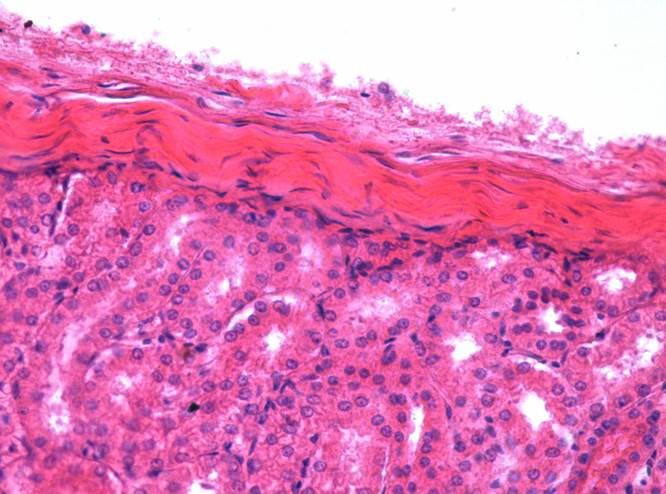

Препарат № 1. «Почка взрослого»,(окраска гематоксилином и

ОГП - 126 эозином).

- Строма почки

- соединительнотканная капсула.

- соединительнотканные прослойки

- Корковое вещество:

3. почечное тельце;

4. сосудистый клубочек;

5. наружный листок капсулы почечного тельца;

6. полость почечного тельца;

7. проксимальный извитой каналец;

8. дистальный извитой каналец.

9. собирательная трубка